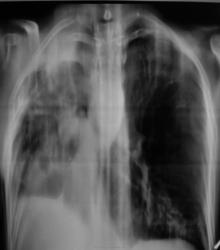

По рентгенограммам фиброторакс как бы неполный, однако, на представленных томограммах правый главный бронх в виде культи, но нечётко видимой. И металл. зажимы в срезы не попали. Там точно всё удалено?

Левое лёгкое с патологией и в нижней доле и в верхней.

Неоднозначно всё

Согласно документам - пульмонэктомия.

Ну пульмонэктомия-значит пульмон эктомия , ничего нового.Только надо иметь ввиду грубое смещение органов средостения и медиастинальная грыжа.

С медиастинальными грыжами понятно. А что ещё светится на месте удалённого лёгкого? При фибротораксе такого не может быть. Когда была операция? И клиники хоть ложку надо.